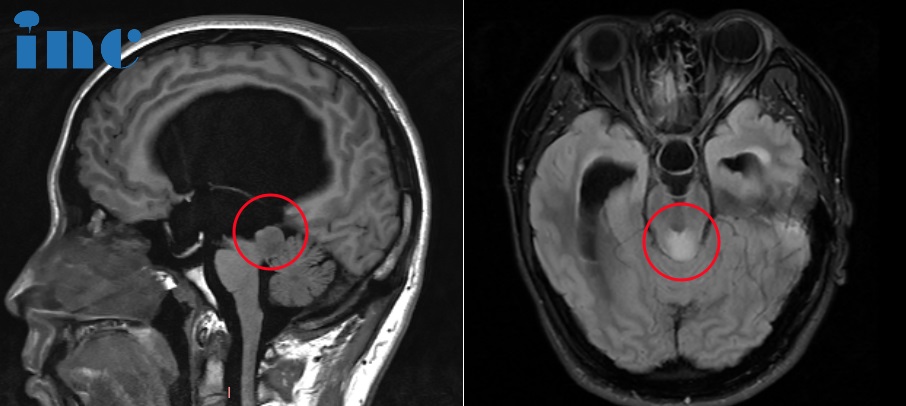

圖片術(shù)前MRI影像

巴教授中腦頂蓋膠質(zhì)瘤示范手術(shù)后影像

圖片術(shù)后MRI影像